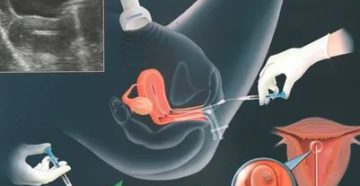

Гиперплазия эндометрия Аномальное увеличение количества клеток эндометрия возникает в результате непрерывной стимуляции матки эстрогенами и…